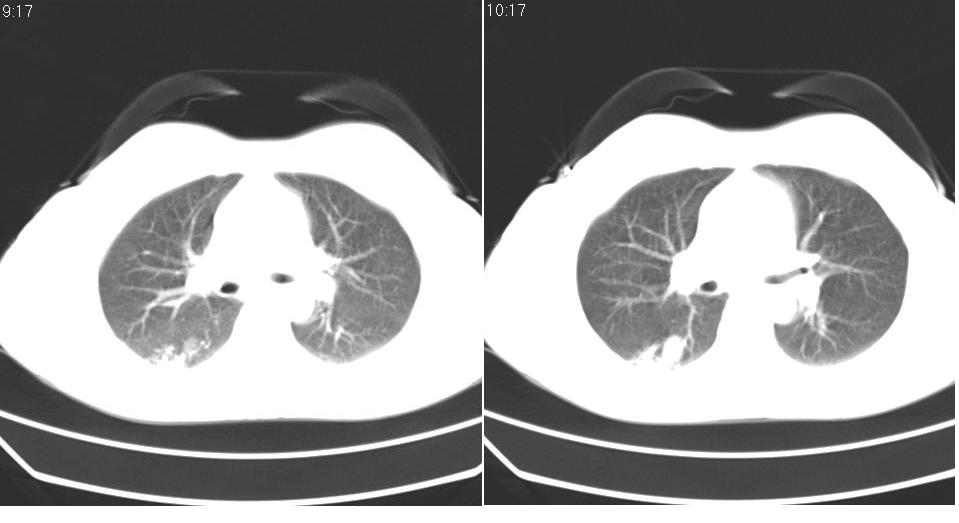

女 40岁,胸片体检发现右肺肿块,无任何症状。

下叶背段多发性小腺泡结节,考虑结核。

肺动静脉瘘可考虑,建议增强

考虑右肺下叶背段继发性肺结核。